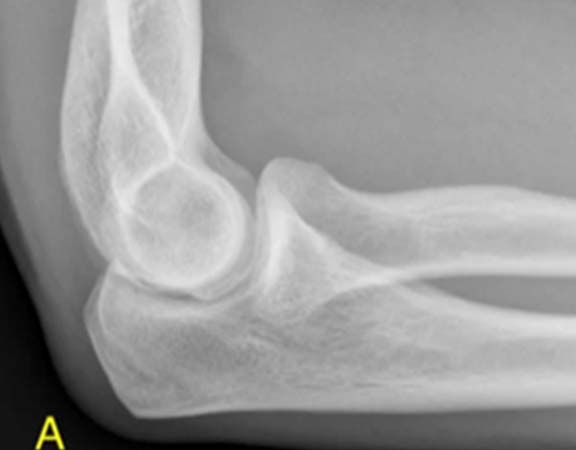

LUXAÇÃO DO COTOVELO

Luxação é a perda de contato entre dois ossos que costumavam estar sempre em contato íntimo e contínuo através da cartilagem. Esse tipo de luxação não é muito comum em cotovelos por terem uma articulação estável, mas quando acontece é, geralmente, quando o indivíduo sofre um trauma, queda ou pancada de alto impacto. Diferente da luxação de ombro, a de cotovelo pode acompanhar fraturas associadas e é de extrema importância que se faça uma radiografia antes de colocar a articulação no lugar. Diante do quadro procure imediatamente um pronto-socorro para os primeiros atendimentos e logo em seguida um médico ortopedista especializado para que ele possa averiguar a situação e dizer qual o tratamento mais adequado. ⠀